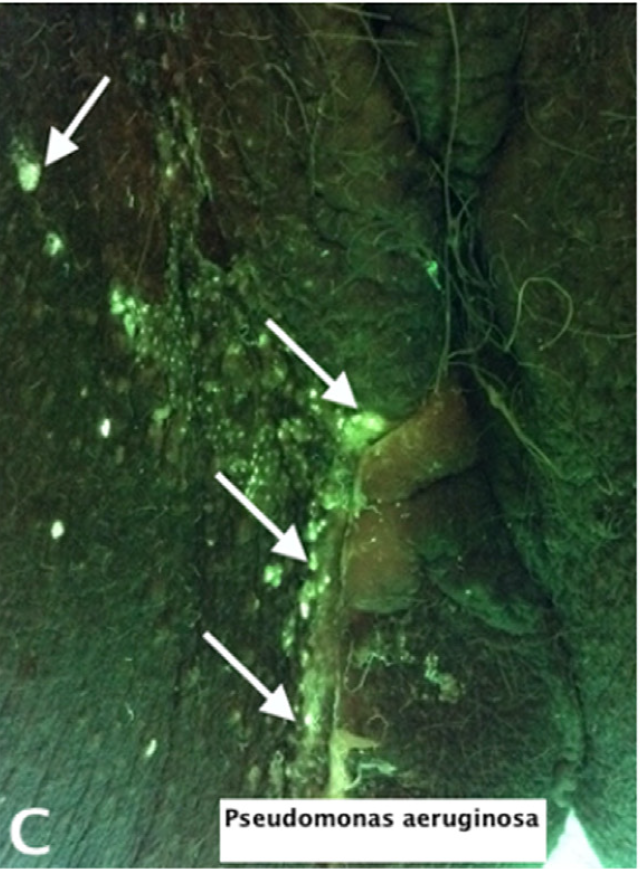

Rapid diagnosis of Pseudomonas aeruginosa in wounds with point-of-care fluorescence imaging

Raizman, R et al. Diagnostics 2021